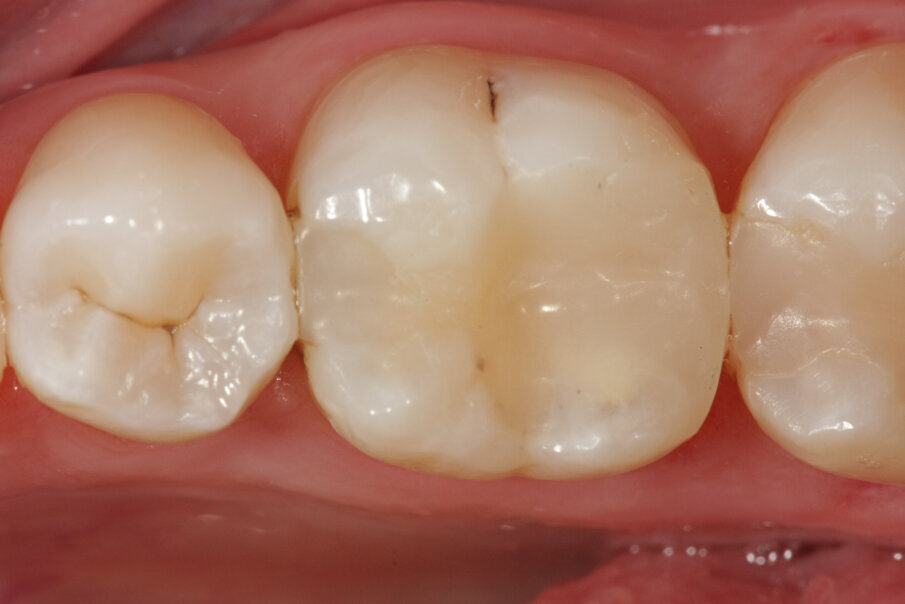

MTA è il materiale che vanta i migliori risultati come materiale da otturazione per la chirurgia apicale. L’MTA è stato associato ad una minore infiammazione, a formazione di nuovo cemento e alla rigenerazione del tessuto periradicolare (Torabinejad e Chivian 1999) (Figg. 4a-4f).

Chirurgia apicale